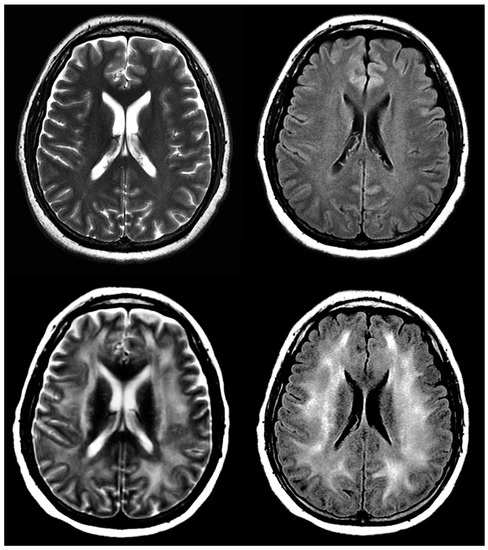

8.5. ICANS and Neurotoxicity

ICANS is the second most common CAR T-cell IRAE after CRS. Onset is most often four days after infusion, and includes a variety of neural symptoms, some severe: encephalopathy, headache, tremor, and aphasia. The onset of symptoms often overlaps with CRS [70]. MRI is the imaging modality of choice for evaluating ICANS due to its superior resolution to CT. Long-term follow-up is recommended to assess for potential cerebral damage [73] (Figure 7).

Figure 7.

A 43-year-old woman with acute myeloid leukemia and history of confusion and disorientation 7 days post-treatment with CAR T-cells. Select images from axial T2 and FLAIR sequences pre- (above) and post- (below) CAR T-cell therapy demonstrating diffuse hyperintense signal abnormality in subcortical and supratentorial white matter, suspected for ICANS.